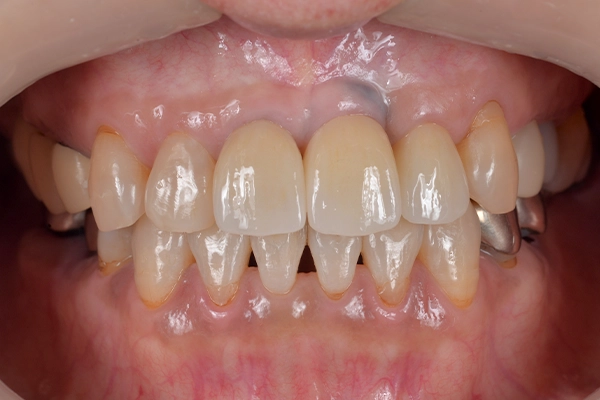

治療前後の比較

正面

before

after

噛み合わせの状態

最終補綴の装着

計3回仮歯を装着した後、最終補綴に向けた被せ物を作製し、装着しました。

担当医からの所感

今回の治療では、矯正治療を併用したことで、見た目の美しさはもちろん、将来的にも安定して使い続けられる(予後の良い)前歯部の審美補綴(被せ物)を達成することができました。仕上がりには患者様にも大変喜んでいただけました。